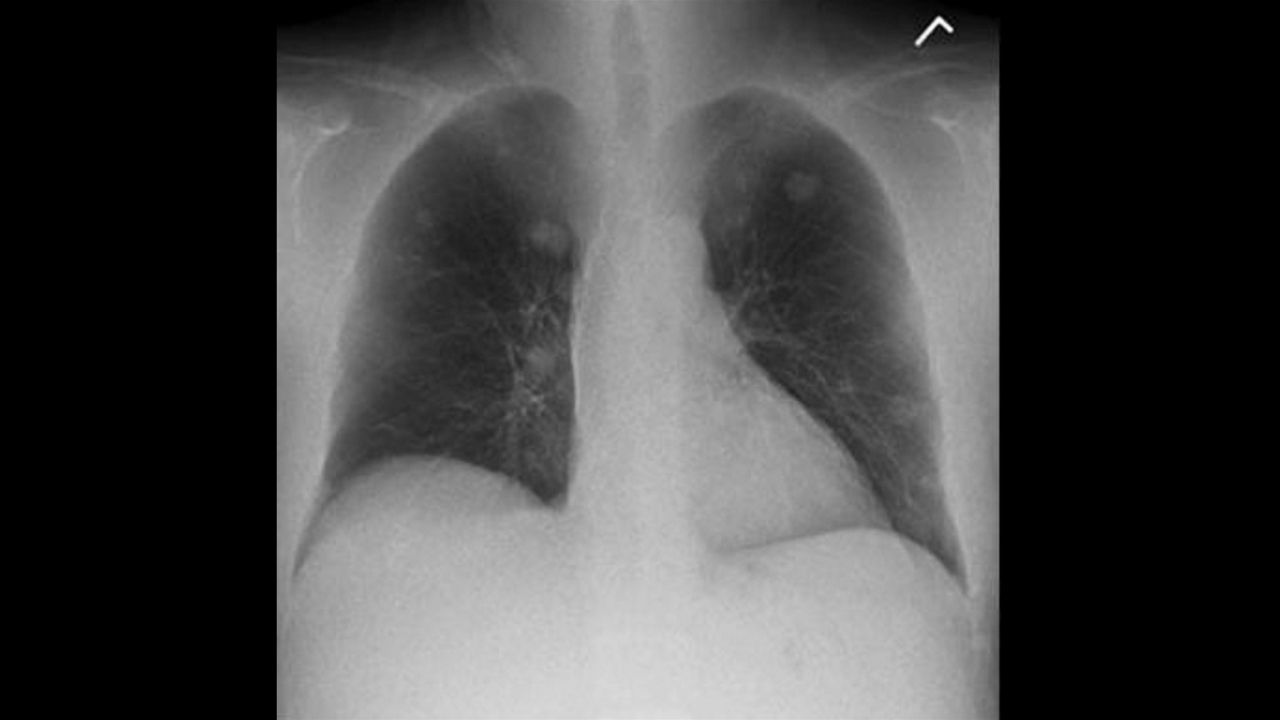

Clinicians rely on standard radiography as the first diagnostic test for most chest, orthopedic and trauma cases

However, advanced imaging is often ordered for complex cases that radiography cannot solve. Tapping additional imaging modalities may result in higher radiation exposure, higher costs, and delays in diagnosis and treatment. Our Advanced Applications provide additional information and more conclusive X-rays to help you make care decisions faster with minimal added radiation.